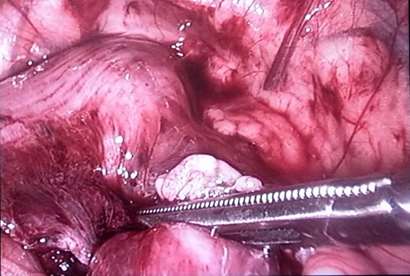

رجیستری بیماران آندومتریوز